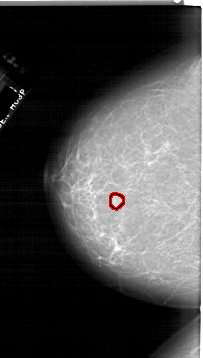

A_1759_1.LEFT_MLO

LEFT_MLO LINES 6781 PIXELS_PER_LINE 3571 BITS_PER_PIXEL 12 RESOLUTION 43.5 OVERLAY

FILE: A_1759_1.LEFT_MLO.OVERLAY

TOTAL_ABNORMALITIES 1

ABNORMALITY 1

LESION_TYPE MASS SHAPE OVAL MARGINS CIRCUMSCRIBED

ASSESSMENT 3

SUBTLETY 4

PATHOLOGY BENIGN

TOTAL_OUTLINES 1

BOUNDARY